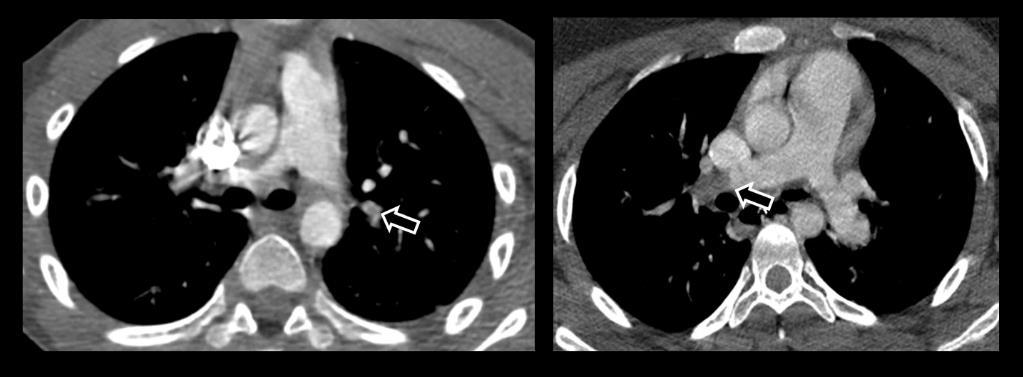

Acute Pediatric COVID-19: CT

3 Phases

Early: "Halo" sign

Local infection

Progressive: Diffuse GGO

Developed: Consolidation

Surr vasc congestion

Inflammation - adj alveoli

Alveoli fill with fluid/cells

Local infection Surr vasc congestion